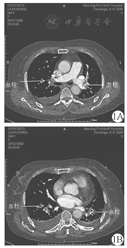

女,64岁,既往有胆道蛔虫病史。2015年10月1日患者无明显诱因下出现腹痛,为上腹部弥漫性胀痛,当时无恶心、呕吐,无腹泻,有一过性神志不清,血压测不出,送至当地医院,当时测血淀粉酶> 900 U/L,腹部超声提示胆囊壁毛糙,腹部CT提示肝周少量积液,腹膜后少量积液,胰腺形态尚正常,诊断考虑为急性胰腺炎合并休克,予以扩容、升压、禁食、胃肠减压、抑酸、抑酶等治疗。患者病情无改善,于2015年10月5日转至我院就诊。在急诊室实验室检查结果如下:WBC计数7.9 × 109/L,中性粒细胞0.821;总胆红素17.6 μmol/L,直接胆红素5.2 μmol/L,丙氨酸氨基转移酶1 578 U/L,天冬氨酸氨基转移酶797U/L,淀粉酶151 U/L,K+ 3.0 mmol/L,Na+ 132 mmol/L,Ca2+ 1.89 mmol/L。以"急性胰腺炎"收入我院普外科治疗。入院时患者神志清楚,精神差,诉上腹部疼痛,伴胸闷,无咳嗽、咳痰、咯血,测血氧饱和度0.90,查体:体温36.8 ℃,脉搏90次/min,呼吸26次/min,血压137/88 mmHg(1 mmHg=0.133 kPa),双肺听诊呼吸音低,双下肺可闻及湿啰音。腹部膨隆,皮下脂肪厚,剑突下偏左侧压痛,Murphy征阴性,无其他异常神经系统体征。因患者存在转氨酶升高、血氧饱和度下降,病因未明,ICU会诊后建议予患者行胸腹部CT增强扫描检查,结果提示双肺门区结节状密度略低,考虑强化不佳的血管可能,请结合临床,必要时行肺部血管CT血管造影检查除外血管性病变或淋巴结等。结合患者病史、症状及CT检查,诊断高度怀疑为急性肺动脉栓塞,遂转入ICU治疗。完善相关检查示B型钠尿肽(BNP)9 196 ng/L、D-二聚体7.2 mg/L,血管彩超提示双下肢静脉未见血栓形成。治疗上予以依诺肝素钠联合华法林抗凝治疗,此后患者氧合改善,腹痛、胸闷症状逐渐好转,复查BNP、D-二聚体、转氨酶进行性下降。10月8日完善计算机断层摄影肺血管造影(CTPA):双肺肺动脉内多发结节状及条状充盈缺损样改变,考虑肺动脉栓塞(图1)。患者肺栓塞诊断明确,继续予以抗凝治疗。10月11日患者病情稳定,转入我院呼吸科治疗,10月21日患者好转出院,出院后继续服用华法林治疗满3个月,随访2年,患者病情无反复。

注:1A:双侧肺动脉主干栓塞;1B:双侧肺动脉分支栓塞